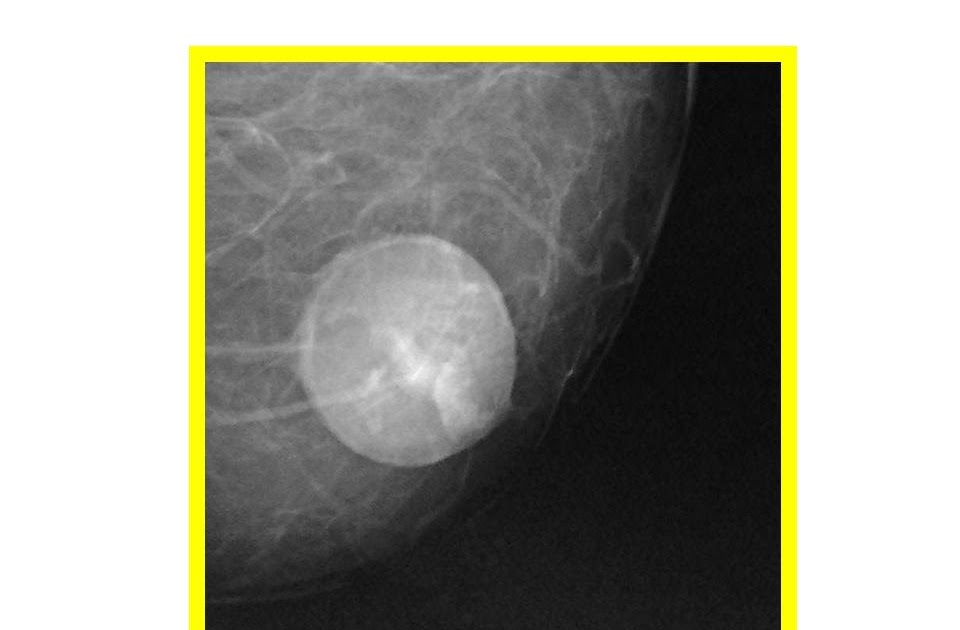

From radiologycases.my

Mammary oil cyst Radiology Cases Oil Cyst Medical Term These cysts might show up on mammograms,. Web the oil cyst is associated with round lesion and wall calcification. In time, calcium builds up around the outside, forming a hard lump. Web fat necrosis and oil cysts are two different conditions that result from the same process: Web oil cysts and areas of fat necrosis can form a lump that. Oil Cyst Medical Term.